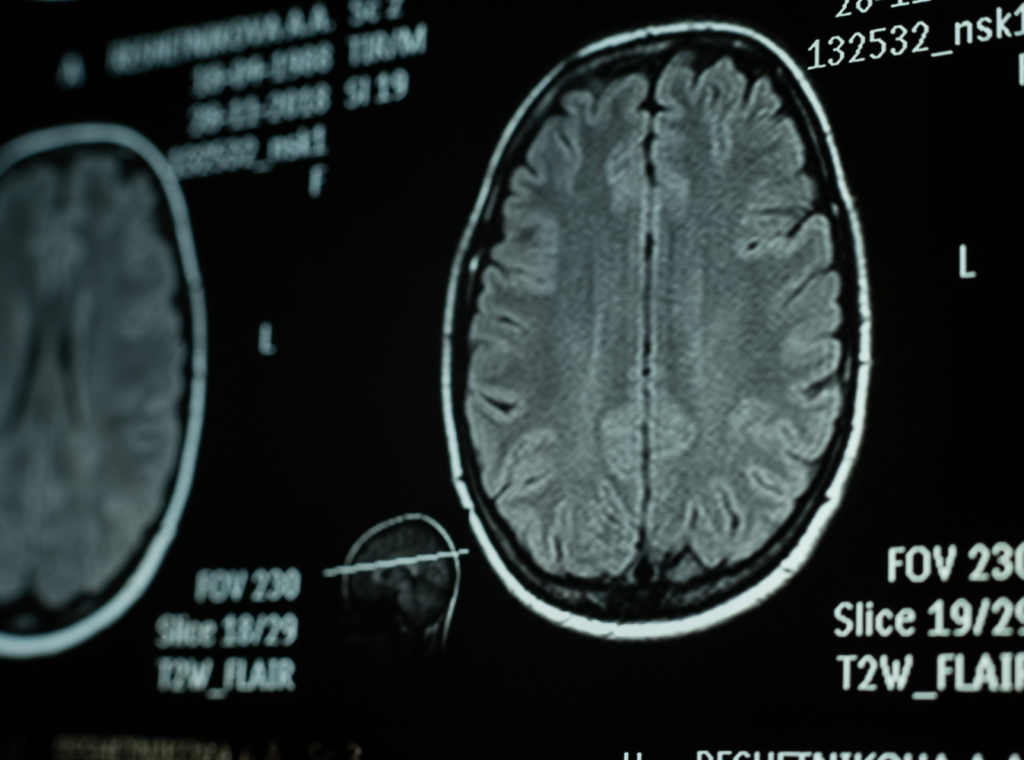

A fall that involves striking the head, whether on the floor itself or on an object during the fall, may result in a traumatic brain injury.

These injuries are particularly significant in premises liability cases because their effects are not always immediately apparent and because they can affect virtually every area of a victim’s life, from cognitive function to emotional regulation to long-term employability.

Why TBI Claims Require Comprehensive Documentation

Traumatic brain injuries often require extensive medical documentation, and their long-term effects may significantly influence claim value. Because symptoms sometimes appear or intensify in the days or weeks after the fall, early and consistent medical evaluation is important both for the victim’s well-being and for building a legally sound record.

A Charlotte slip-and-fall attorney works to ensure that the documented picture of a TBI accurately reflects its actual impact rather than an incomplete early assessment.